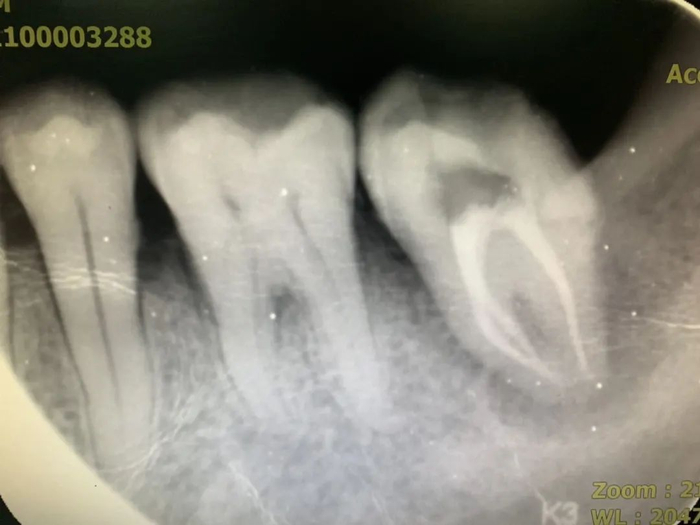

2014级口腔医学(八年制)佟佳儒印象最深的是口腔解剖生理学课程。画了一页页的牙体外形、背了一遍遍的牙齿根管走行及数量让她意识到,每一颗牙齿都不能孤立的看待,每一颗牙齿都有其解剖形态的特殊性。

“走上临床之后慢慢发觉,所有的细节性知识都有被用到的地方,所谓细节决定成败,感谢口解生教会我这些细节性知识。”佟佳儒说。